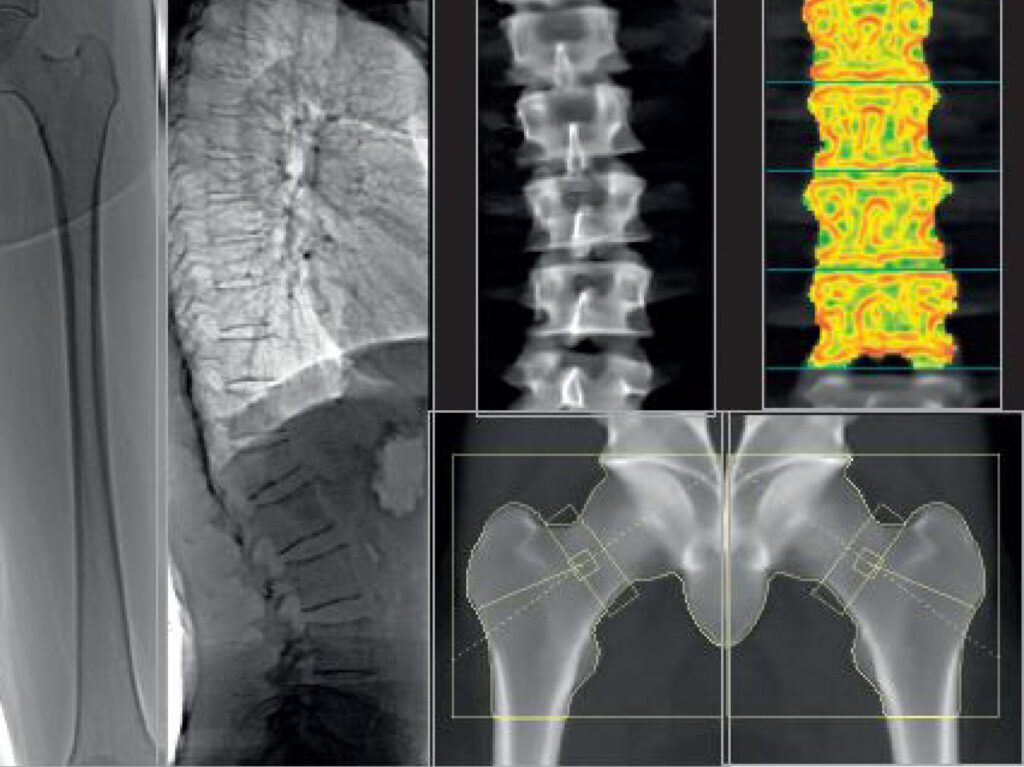

L’ostéodensitométrie ou densitométrie osseuse est aujourd’hui la technique de référence pour l’établissement d’un diagnostic précis de l’ostéoporose.

Cet examen utilise les rayons X et consiste à mesurer la densité minérale osseuse (DMO).

Dans le cas de cet examen, l’os étudié (généralement la hanche, les vertèbres ou le poignet) est soumis à un rayonnement de photons. Plus l’os est dense, moins les photons qui arrivent en bout de traversée seront nombreux.